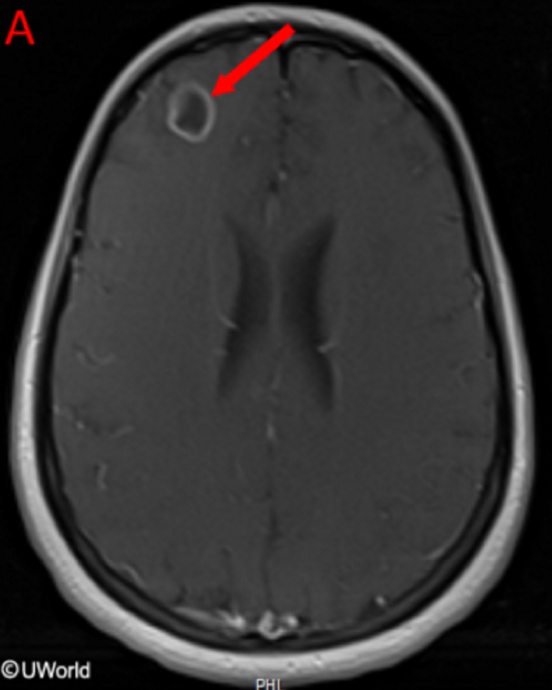

This patient has a primary CNS lymphoma. The presence of EBV DNA in the CSF is specific for this condition. MRI reveals a weakly ring-enhancing mass that is usually solitary and periventricular.

Toxoplasmosis is a good differential diagnosis; however, it is unlikely in this patient since he is receiving trimethoprim-sulfamethoxazole. MRI reveals multiple, ring-enhancing, spherical lesions in the basal ganglia. A positive Toxoplasma serology is quite common in normal subjects in the United States, and is therefore not specific for toxoplasmosis.